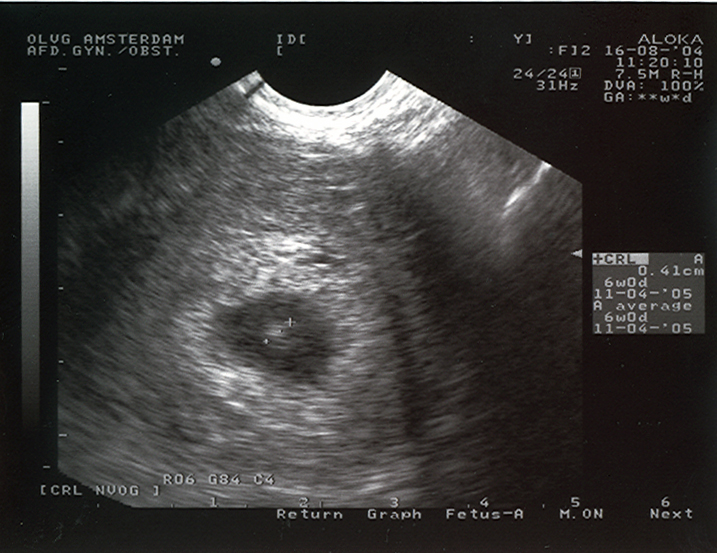

Ultrasound at 28 days

Ultrasound picture of a 4-week old pregnancy. On the right you can read the size: 0,41 cm. This means that the mother is about 12 days over time. If a pregnancy like this is unwanted, we can end it on our ship when outside the 12 mile zone.